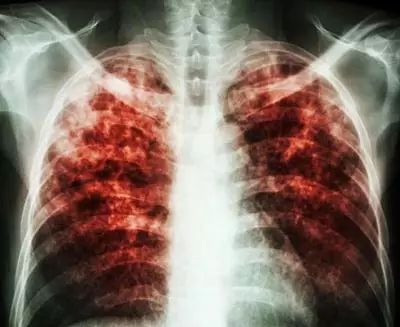

慢阻肺肺氣腫總是治不好?你可能踩到了這三大雷區(qū)!

慢阻肺跟高血壓一樣也是一種慢性病,早期治療事半功倍,長期而有計劃的綜合治療是治療疾病的關(guān)鍵所在。

其實,慢阻肺跟高血壓一樣也是一種慢性病,早期治療事半功倍,長期而有計劃的綜合治療是治療疾病的關(guān)鍵所在。

慢阻肺屬于冬病,冬天容易發(fā)作。而現(xiàn)在是夏天,多數(shù)患者的病情處于穩(wěn)定期,各種癥狀都比較輕。大部分慢阻肺患者卻忽略了治療,錯失了良機(jī)。有種說法是“急性加重期是救命的,穩(wěn)定期才是治病的”,因此提倡大家冬病夏治。

慢阻肺肺氣腫是慢性病,需要慢慢治療。患者應(yīng)該有計劃地綜合性的長期治療,以達(dá)到防微杜漸的作用,減緩疾病發(fā)展的速度,減少急性發(fā)作和并發(fā)癥的發(fā)生。

所以,治療肺氣腫、慢阻肺這些慢性病,切莫錯失良機(jī),不可急于求成,更不能見好就收。關(guān)鍵在于長期堅持疏通氣道、排出黏痰、排出二氧化碳,輕輕松松就能在家治療,減少發(fā)病,減少住院。